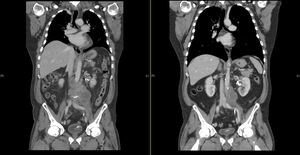

A PET-CT performed at the end of September 2017 revealed that the retroperitoneal tumor was progressing rapidly in size (Figure 1). In addition, it had also metastasized to multiple abdominal lymph nodes, including retroperitoneal, mesenteric, posterior inferior mediastinal and left retroclavicular localizations. Palliative chemotherapy (carboplatin and etoposide) was initiated in order to slow down the rapid tumor growth. It was continued for 2 cycles in the following 6 weeks, which led to a mixed response in the patient. The chemotherapy regimen was continued for further 6 weeks, as the patients achieved a partial response with a regression of the clinically significant lesions. In addition, between December 2017 and January 2018, palliative radiotherapy was conducted due to incipient vena cava infiltration. The subsequent CT showed a regression of the irradiated retroperitoneal tumor regions, whereas a progression of the tumor was evident in the supraclavicular, paraoesophageal and tonsillar regions.

In February 2018, treatment with avelumab (10 mg/kg body weight IV) was initiated. After 3 months of treatment, the disease had stabilized and partial remission was achieved after 9 months (Figure 1). The patient tolerated the regimen very well, showing no adverse effects. In March 2019, due to a localized tumor growth, the paratracheal lymph node was treated with radiation therapy. Afterwards, a local complete response and a systemically ongoing partial response was achieved (-51.3% of the total tumor volume according to iRECIST criteria).